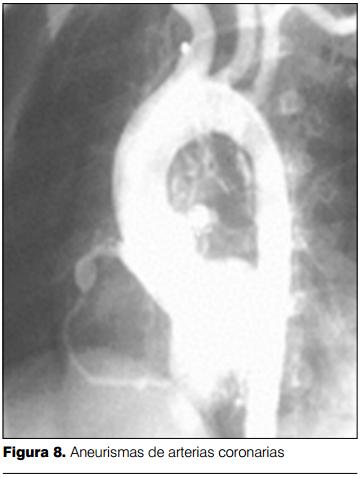

Dilatación y aneurismas coronarios

Aproximadamente el 15-25% de los niños no tratados desarrollan anomalías coronarias, incluyendo dilatación difusa y formación de aneurismas. La dilatación coronaria puede detectarse a partir de los 7-10 días de iniciada la enfermedad, pero es entre la tercera y cuarta semana en donde se produce el pico de mayor incidencia (35,36).

El desarrollo de aneurismas coronarios se vincula con el riesgo de muerte súbita, por trombosis coronaria e infarto agudo de miocardio. En el seguimiento a largo plazo de los pacientes con dilataciones coronarias y aneurismas, se evidenció que el retroceso de las anomalías coronarias es un hecho frecuente, hasta en 50% de los casos, y en los restantes se evidenció disminución del tamaño de aneurismas, con o sin estenosis coronaria (25%), retroceso de aneurismas pero con estenosis coronaria (15%) y en los restantes finas irregularidades de los vasos coronarios pero sin estenosis (10%). En seguimientos a largo plazo, se estima que 40% de los pacientes con aneurismas coronarios persistentes y estenosis coronaria desarrollan infarto de miocardio (38).

La forma más severa de afectación coronaria es el desarrollo de aneurismas gigantes (³8mm). Estos aneurismas tienen menos probabilidad de retroceder y son frecuentes las complicaciones (trombosis, ruptura, estenosis). El porcentaje de niños con EK que desarrollarán aneurismas gigantes es variable, reportándose valores de entre 1 a 4%, con una mortalidad elevada (39).